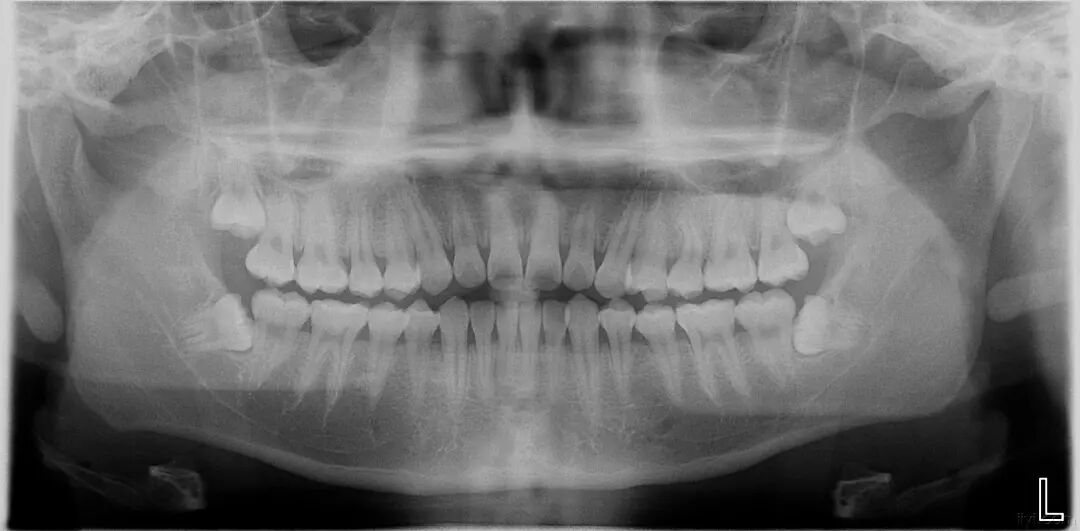

口腔全景片,顾名思义就是可以把全口牙齿都展现出来的一种牙片,这是牙科比较常见的片子,一般就是这样的:

曲面断层片怎么看科普知识:你会看牙片嘛?今天手把手教你看!_https://www.jmylbn.com_新闻资讯_第2张

牙片分为局部牙片和全口的曲面断层片。

全口的曲面断层片可以拍摄全口的所有牙齿以及关节区。

拍摄这种牙片可看到有无智齿、多生牙、根尖周炎、多少颗蛀牙等。

特别是在做牙齿矫正、种植牙、拔智齿等的时候一般需要拍摄这种牙片。